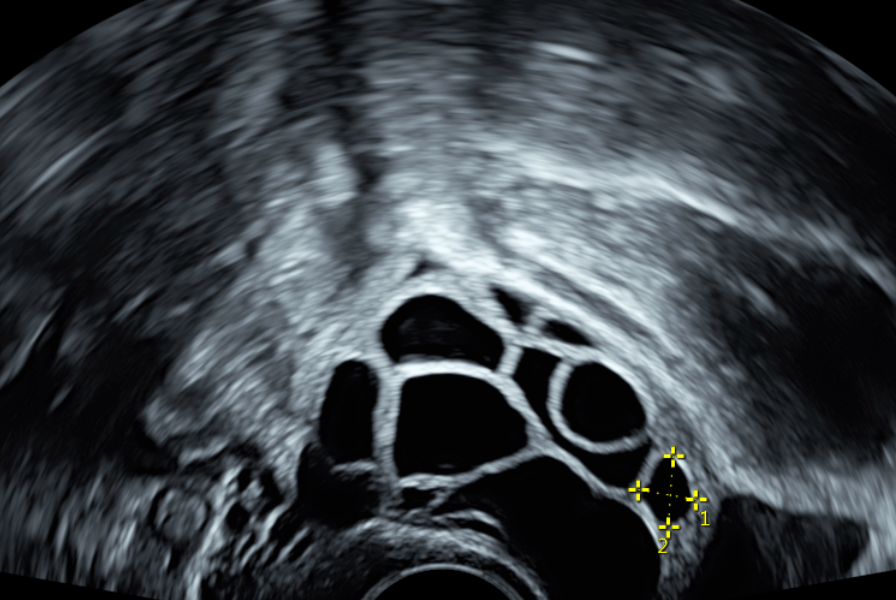

(以上圖示並非當事人,僅為多囊案例參考)

雖然卵子在超音波下看起來堆滿了滿滿的卵泡,但是卻大多數都是不成熟且未能排出的卵泡堆積在卵巢。